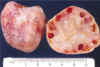

For seminomas of the testicles, provide epidemiology, description, diagnosis, prognosis, and pathology (gross and micro)

- Epidemiology: most common testicular tumor, not common in infants

- Description: remains localized within tunica albuginea

- Diagnosis: radiosensitive (respond to radiotherapy), HCG production is rare

- Prognosis: presents in clinical stage I (good prognosis); late metastasis

- Pathology:

- Gross: homogenous pale tan parenchyma (pic)

- Micro: fibrovascular septae with lymphocytes